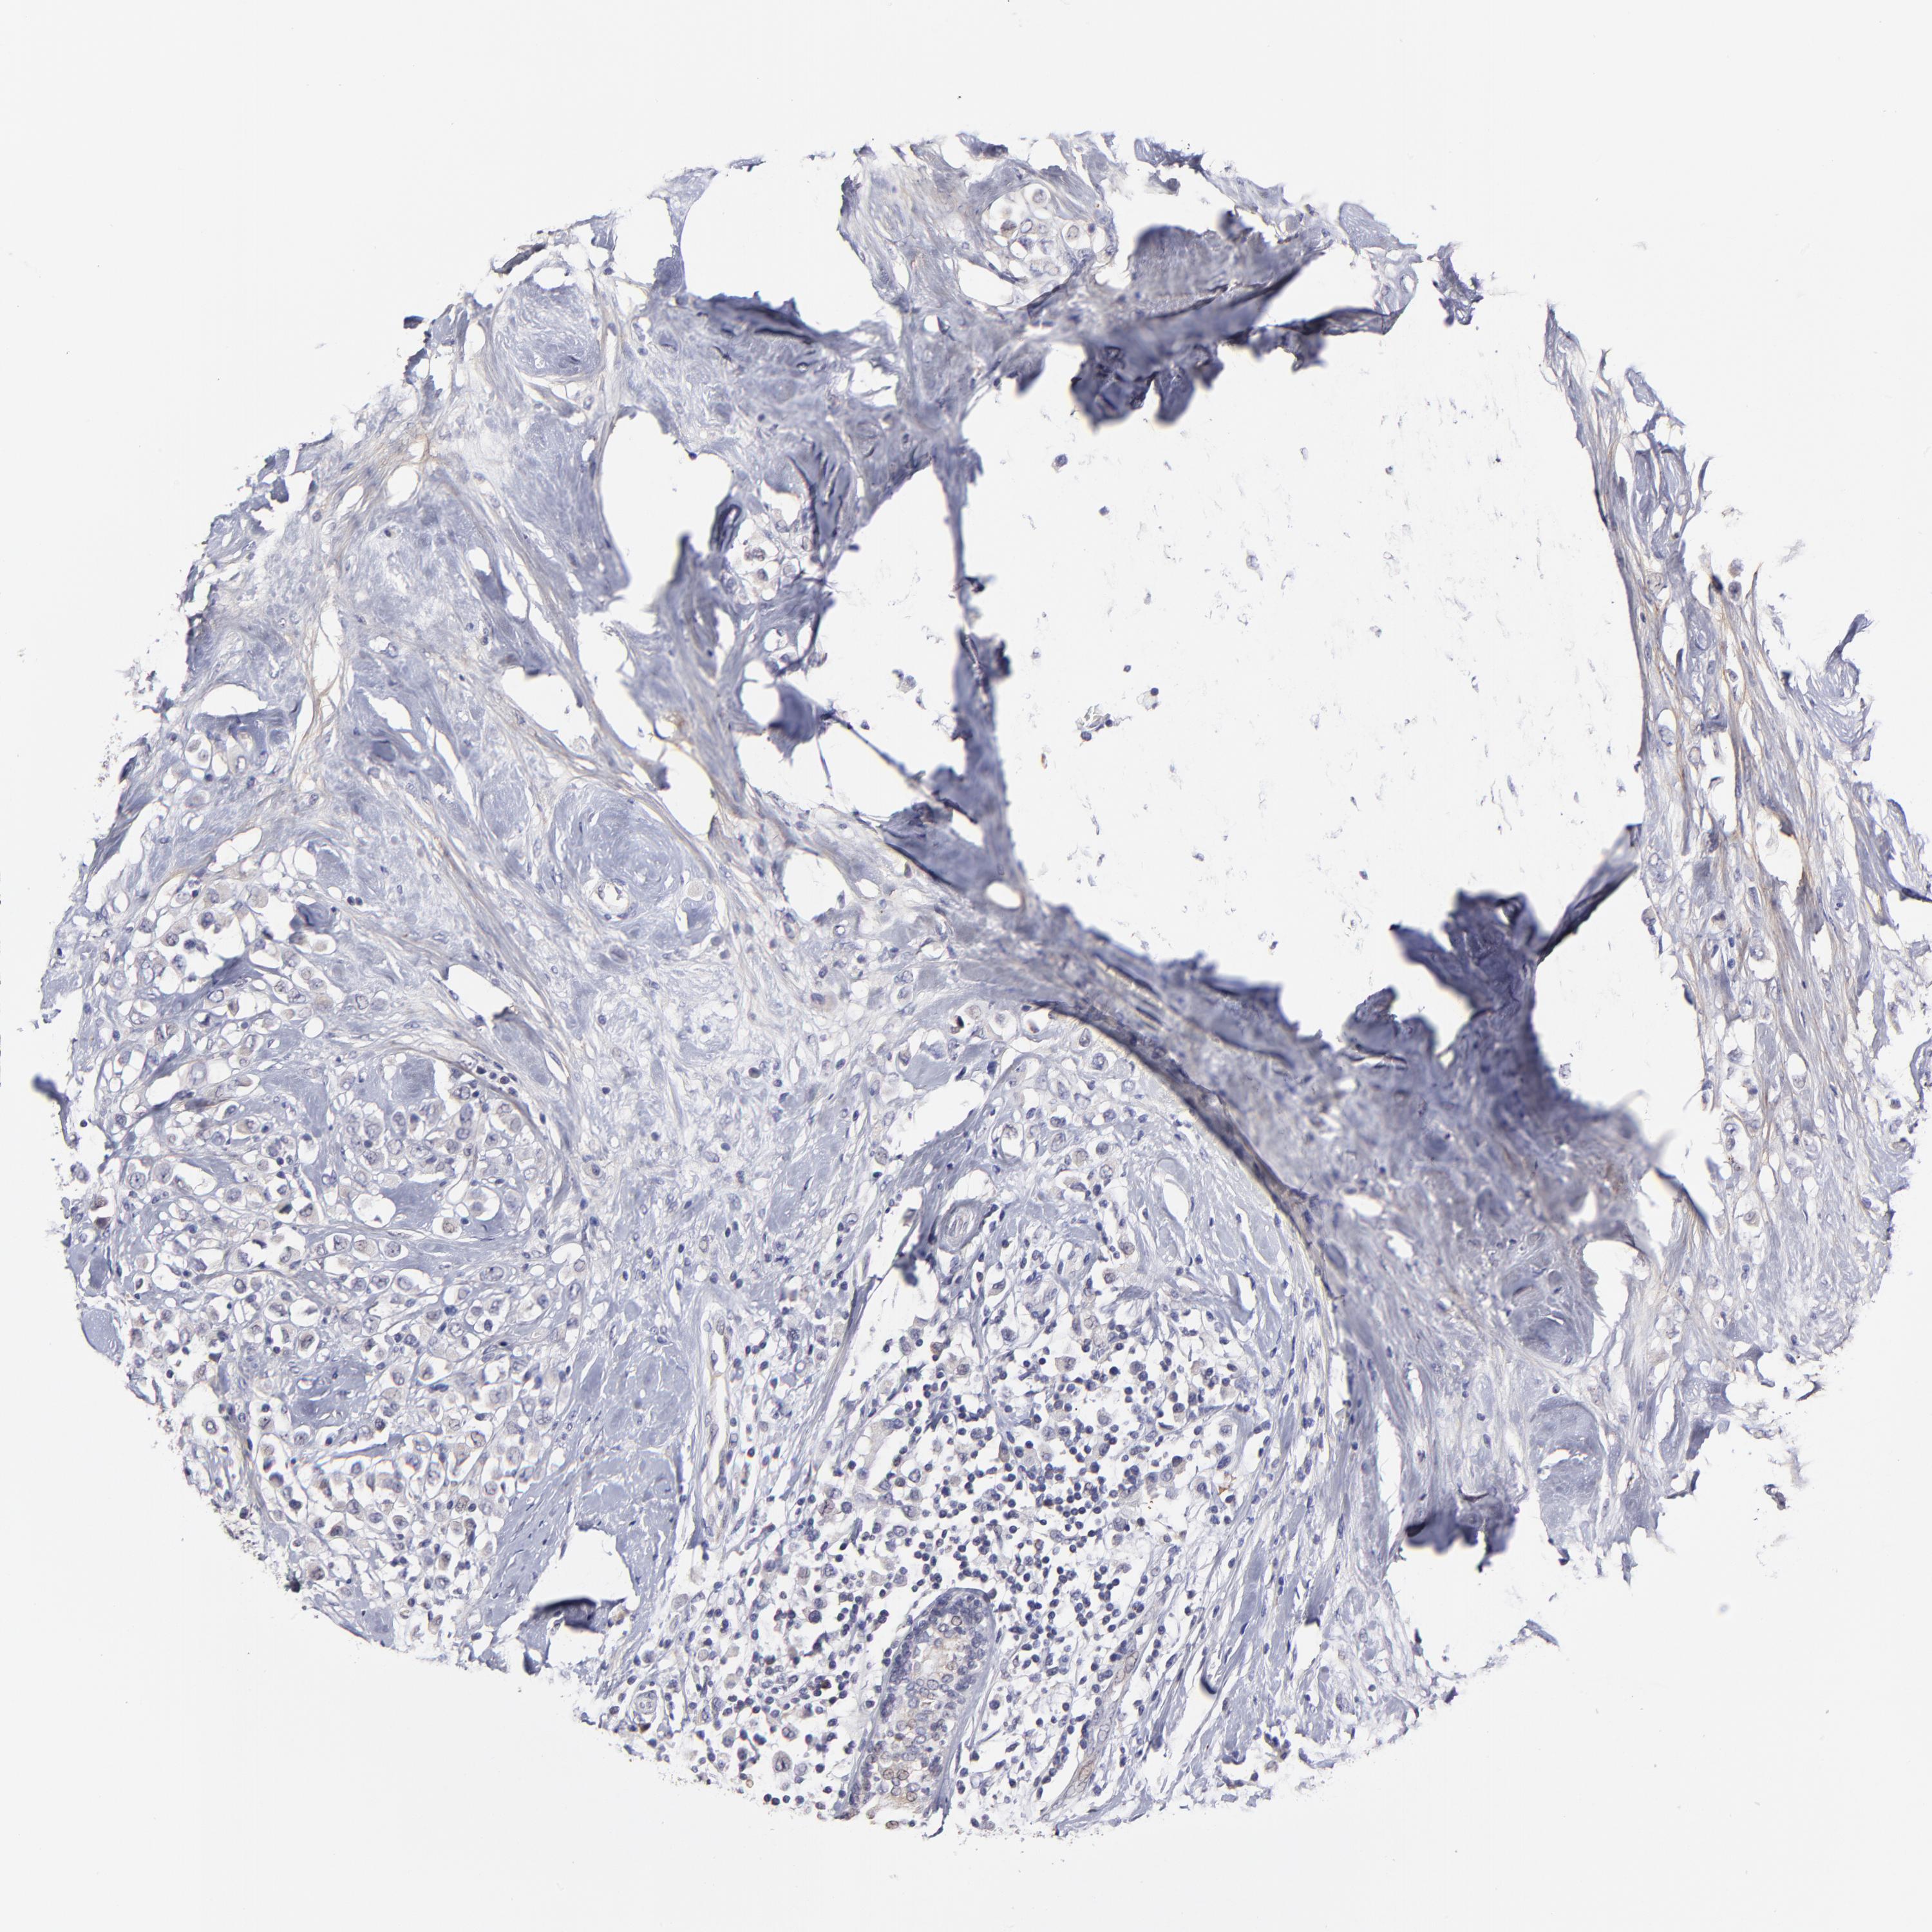

BRCA TCGA BRCA VALIDATION PROTEIN EXPRESSION

ANTIBODIES

AND

VALIDATION